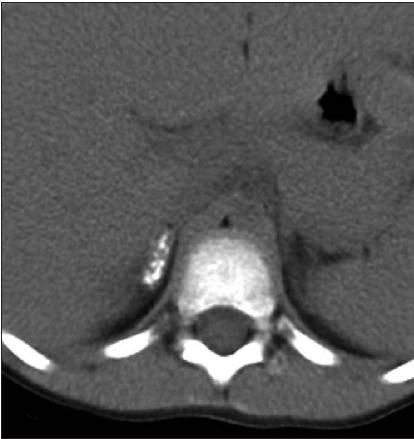

3. A limited CT scan of the upper abdomen was obtained. What are the findings in the upper abdomen?

What are the findings in the upper abdomen? (D is the correct choice.)

Whether the CT scan was absolutely necessary in this patient's case is open to debate; however, this is in fact how the saga unfolded. Indeed, in the right suprarenal fossa are dystrophic, benign-appearing calcifications scattered throughout the right adrenal gland, which is of normal contour and size. There were no renal or liver calcifications, nor were there any rib fractures. It would be unwise to rely on a CT scan to show gallstones, if they were present. CT is notoriously misleading in this regard. Because gallstones vary in composition and density, they may be present but completely inapparent on CT scans. However, we had already eliminated this possibility on the sonogram.

4. Do the findings on the CT scan explain the patient's symptoms, now described as "pain on the entire right side of her body"? (B is the correct choice.) No.